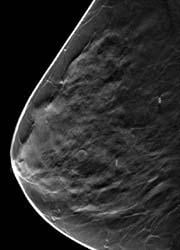

Digital breast tomosynthesis (DBT) is a U.S. Food and Drug Administration (FDA)-approved 3-D imaging modality that can identify and characterize individual breast structures without the confusion of overlapping tissue. It is especially beneficial for women with dense breasts.

Dense breast tissue can obscure an underlying cancer, or conversely mimic a cancer when none exists. Approximately 15 to 20 percent of breast cancers cannot be detected using traditional 2-D mammography, especially in women with dense breast tissue.

During a tomosynthesis exam, 15 digital "projection" images are captured as the system arcs over the breast during a short four-second scan. These images are then digitally reconstructed into a series of high-resolution one-millimeter slices that can be reviewed individually or played back in a cine loop.